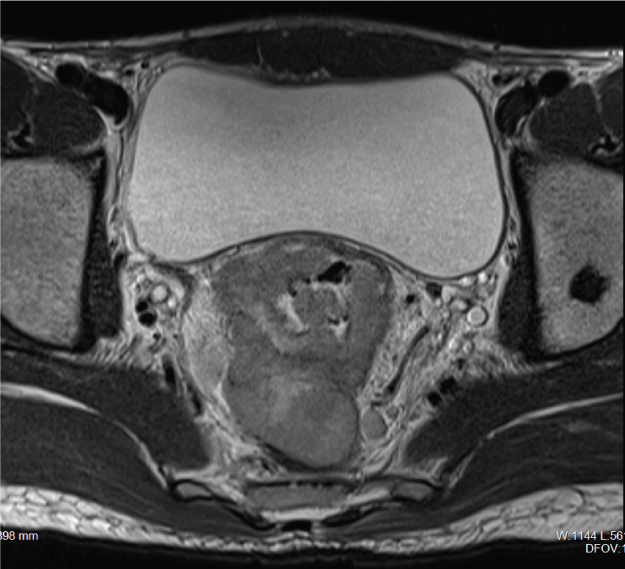

High resolution T2W axial image showing infiltrative malignant rectal mass (arrow) with perirectal lymphadenopathy.

A 24-year-old male presented to the institute in GI Oncosurgery Department as a diagnosed case of metastatic adenocarcinoma of rectum. The cross sectional imaging done in the radiology department also showed evidence of polypoidal infiltrative rectal mass with perirectal, bilateral iliac and paraaortic lymphadenopathy and bony lesions [Table/Fig-1]. Patient underwent abdominoperineal resection with abdominal lymph node dissection after receiving neoadjuvant chemotherapy and radiotherapy. Thereafter, patient received multiple cycles of FOLFOX-4 based chemotherapy and was on regular follow up for one and a half years, when he presented with complain of painless right scrotal swelling. USG examination revealed multicystic septated lesion involving head and body of right epididymis measuring 3.0 x 1.6 x 3.6 cm. On colour Doppler imaging there was no internal vascularity [Table/Fig-2a,b]. Mild ipsilateral hydrocele was also present. Bilateral testis were unremarkable. Imaging differentials of cystic lymphangioma, loculated hydrocele, epididymal cysts and spermatocele were considered and patient underwent excisional biopsy. Histopathological evaluation was suggestive of epididymal lymphangioma as evidenced by microscopic findings of network of multiple irregular dilated cystic spaces lined by single layer of endothelium with stromal infiltration by lymphocytes. Postoperative period was uneventful and the patient was discharged in stable condition. Follow up with USG imaging after three months showed no evidence of recurrence.